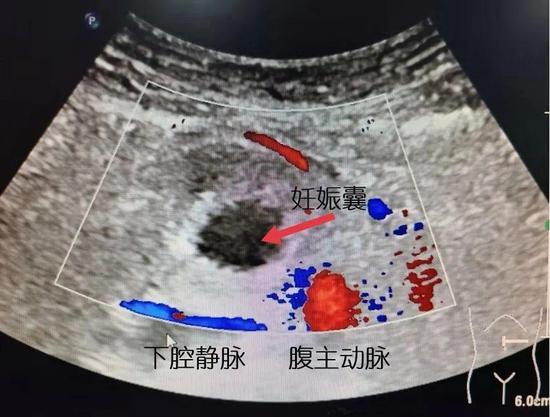

超声科值班医生杨柳芳为雨芬做了B超检查,发现并未在患者子宫内外寻找到妊娠囊。疑惑之下,杨柳芳进一步扩大了超声检查范围,竟然意外发现在雨芬的腹膜后腹主动脉旁有一囊性包块,同时见到妊娠囊踪迹,也就是说,妊娠囊不在子宫里,而在后腹部!“腹腔内妊娠可疑”,杨柳芳马上给出诊断意见。

备好充足血液、建立锁骨下静脉通路……准备就绪,腹腔镜下,林婷婷拨开肠管,腹主动脉及下腔静脉区域一巨大血肿进入视野,直径约15cm。

陈锦果与倪益树互相配合,用超声刀小心翼翼,抽丝剥茧般分离患者妊娠囊紧贴的腹主动脉及下腔静脉,生怕出一点差错,直至完整剥除妊娠病灶,用时整整50分钟,手术成功。